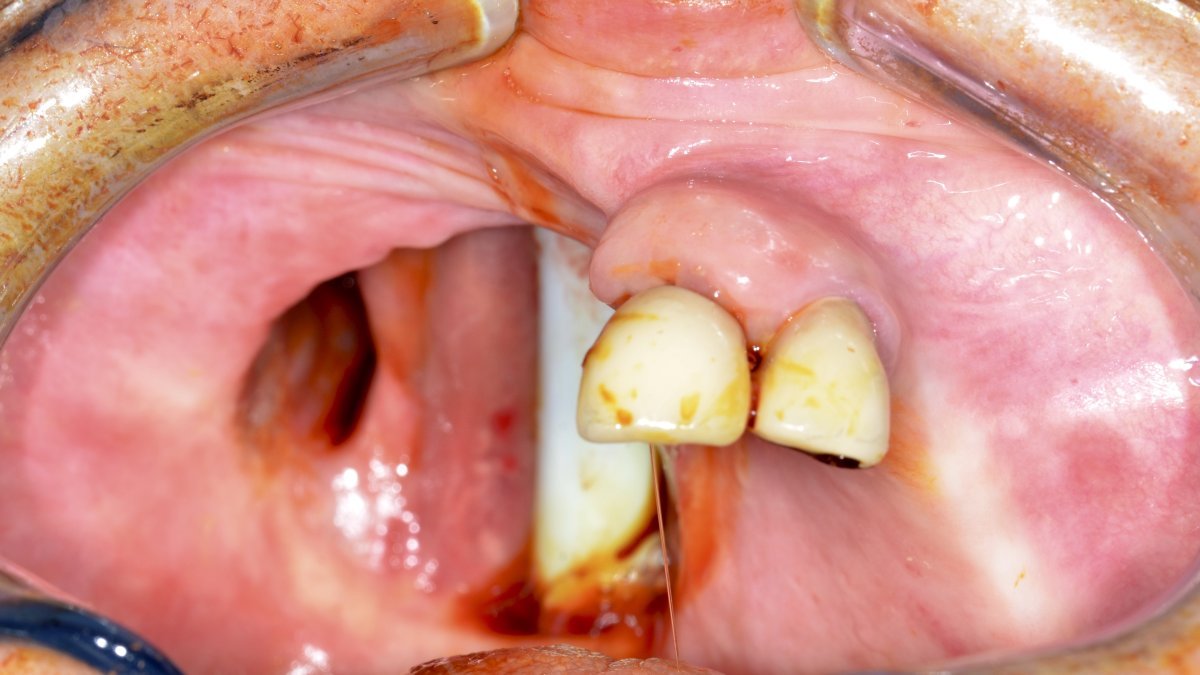

Pre-op maxillary defect